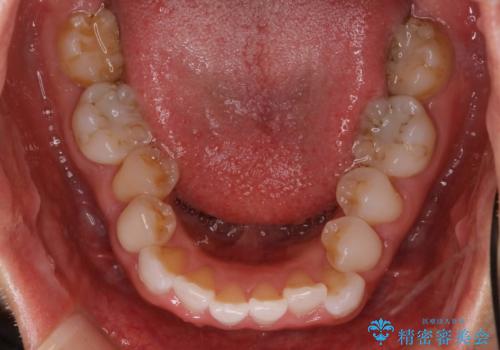

抜歯せずに八重歯のマウスピース矯正

- 非抜歯・遠心移動+IPR+拡大 によるマウスピース矯正を計画した。

八重歯がシビアな場合、抜歯をしないと治せないケースもありますが、奥歯の位置関係を修正したり、歯のサイズダウンを行うことで、抜歯をせずに改善できる場合もたくさんあります。